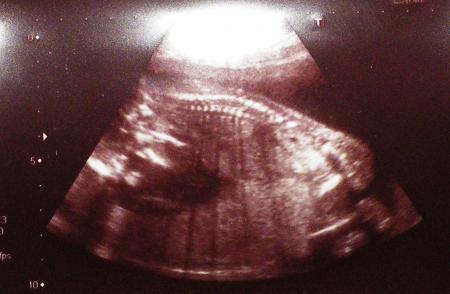

Leider musste ich es abfotografieren, weil ja unser Scanner nicht angeschlossen und installiert ist. Natürlich finde ich die CD nicht und das Kabel ist verschollen. Irgendwo bei dem Umzug ist es uns abhanden gekommen. Muss demnächst mal ne Liste machen mit verschwundenen Sachen und suchen Aber vielleicht könnt ihr auch so etwas erkennen. Links sieht man das Gesicht leicht im Profil, dann die Wirbelsäule und am Ende Po und angezogene Beinchen. Soll ja auch so sein Lieben Gruß Micha

Auch ein Rücken kann entzücken Sonja